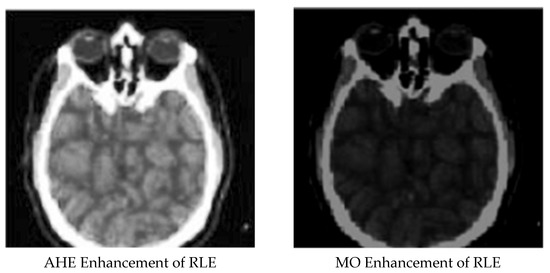

Enhanced and Compressed Output

| 9 | RLE compressed image | 0.48970346 | 0.299972986 | 43.72625764 |

| 10 | AHE enhancement for RLE compressed image | 0.87101654 | 0.000629014 | 70.50874365 |

| 11 | MO enhancement for RLE compressed image | 0.81224123 | 0.001335176 | 69.85366112 |